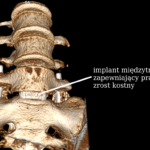

Zespolenie międzytrzonowe

- Wprowadzenie materiału kostnego:

- autograft (często z wyrostków),

- allograft / substytuty,

- Implantacja cage’a TLIF (PEEK / tytan),

- Kontrola fluoroskopowa.